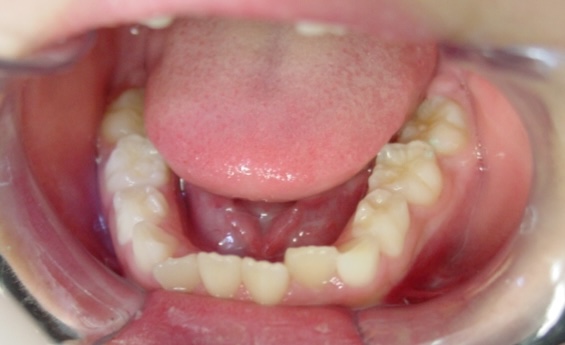

矯正後

| 通院目的 | 永久歯を抜かずに歯並びを治したい。 |

| 処置内容 | バイトブロック・プレート拡大処置・ディスタライザー・インビザライン・オーソテイン・マルチブラケット装置・プリフィニッシャー |

| デメリット・院長コメント | 永久歯を抜かない治療のデメリットは、治療期間が長いことです。 ただし、その後の人生の長さを考えると、健全な小臼歯を2本または4本抜歯の矯正治療よりも、はるかにメリットがあるといえます。 また、アーチが小さくならないので、舌が後ろに押し込まれないためいびき防止につながり睡眠の質の向上にもつながります。 |